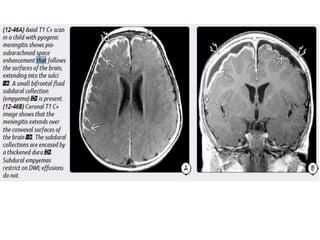

Imaging

MR is the procedure of choice for evaluating potential empyemas. T1

scans show an extraaxial collection that is mildly hyperintense relative to

SDEs are typically crescentic and lie over the cerebral hemisphere. SDEs

often extend into the interhemispheric fissure but do not cross the midline.

EDEs are biconvex and usually more focal than SDEs. EDEs may cross

the midline, confirming their epidural location